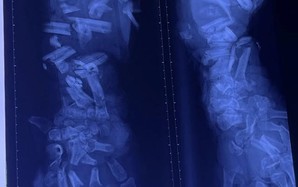

Người phụ nữ ợ hơi, tức ngực đến bệnh viện phát hiện điều bất ngờ

(NLĐO) - Bị ợ hơi sau ăn rồi tức ngực cách đây 2 năm, người phụ nữ đi điều trị nhiều nơi nhưng bệnh tình không thuyên giảm.